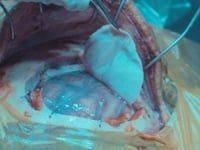

La cirugía en paciente despierto (awake surgery) es una técnica neuroquirúrgica avanzada que permite extirpar tumores cerebrales —como los gliomas— mientras el paciente se mantiene consciente, en condiciones controladas y sin dolor. Esta metodología se utiliza especialmente cuando el tumor se encuentra en áreas cerebrales críticas para funciones como el lenguaje, la memoria, la música, la emoción, la planificación o la movilidad.

Durante la intervención, se realiza un mapeo cerebral intraoperatorio en tiempo real. Mediante estimulación directa del cerebro y monitoreo de tareas específicas (hablar, contar, identificar imágenes o sonidos, mover extremidades), el equipo quirúrgico identifica las redes neuronales esenciales. Este abordaje, conocido como mapeo cognitivo multimodal, va más allá de las funciones motoras o del lenguaje, y evalúa también procesos complejos como la cognición, las emociones y la creatividad.

Este enfoque permite alcanzar lo que se denomina un equilibrio oncofuncional: lograr la mayor resección posible del tumor (objetivo oncológico) con la menor alteración funcional (objetivo neurofuncional). Está demostrado que una resección amplia mejora el pronóstico en gliomas, pero hacerlo sin afectar las redes cerebrales críticas es fundamental para preservar la calidad de vida.